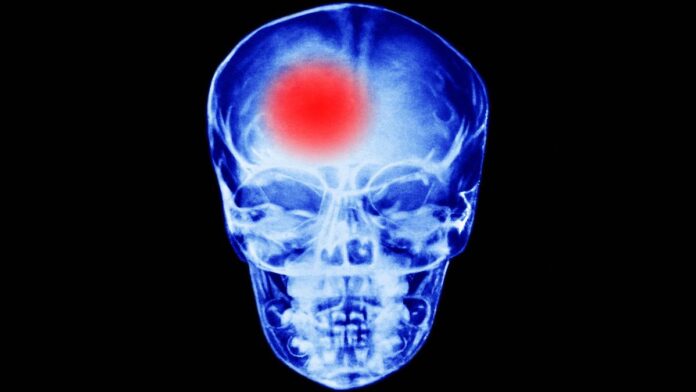

Infarto Cerebral primera causa de discapacidad en adultos mayores

Autoridades del Instituto Nacional de Neurología y Neurocirugía “Manuel Velasco Suárez”, explican los tipos de infarto cerebral.

“La enfermedad vascular cerebral se refiere a la afectación de los vasos en el cerebro, que pueden ser de dos tipos en especial: uno, cuando se incluye un vaso que es lo que se denomina como isquemia cerebral, está tapado un vaso y se infarta una parte del tejido cerebral“. Antonio Arauz Góngora, director general del INNN “Manuel Velasco Suárez”

El segundo es la ruptura de un vaso sanguíneo, una hemorragia cerebral.